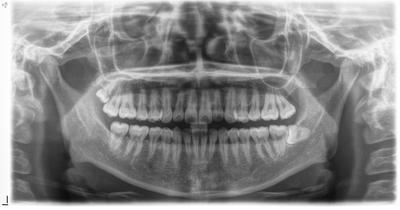

親知らず疼痛で来院。(そもそもは右下親知らず)

前医では抜歯できない、大きな病院を紹介すると言われ、相談に来られた。

問題なく10分位で抜歯完了。

繊細な切開、抜歯を心がけたので、腫れ痛みもほとんどなし。

左下、左上の親知らずも埋伏歯であったが既に当院で抜歯済であり、右上の親知らずは様子見。

難易度は5段階の2程度。

歯周外科処置を多く行っている私には。

前医はこの程度の抜歯も行えず、インプラント云々と言っても説得力ないがこれが現実。